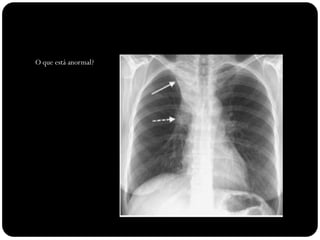

O que está anormal?